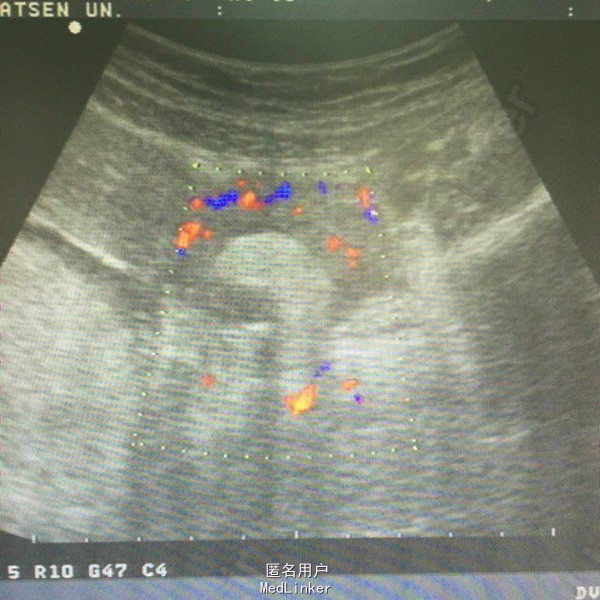

肛查:双侧附件区个扪及一肿物,右侧6*6cm,无压痛、反跳痛,左侧3*3cm,有压痛,无反跳痛。阑尾彩超未见明确显示。血常规白细胞及中性粒细胞百分率升高。彩超子宫双附件:双侧附件区混合性肿块,右侧60*54mm,左侧38*21mm,呈面团征,后方回声增强,考虑畸胎瘤可能性大。

诊断:双侧卵巢畸胎瘤,左侧卵巢蒂扭转。行腹腔镜检查,术中见右侧输卵管扭转180°,卵巢表面血运良好,予行双侧卵巢囊肿剔除,标本中查见毛发及油脂。术后病理:双侧卵巢成熟性畸胎瘤。